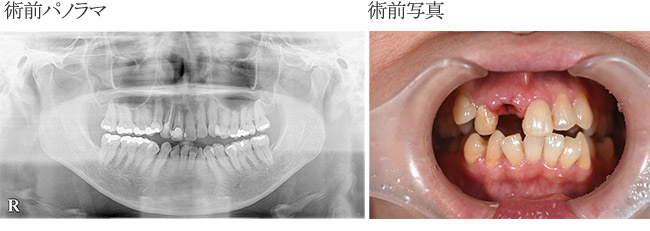

з—ҮдҫӢ2

жӯҜгҒ®з ҙжҠҳгҒ«гӮҲгӮҠз–јз—ӣзҷәз”ҹ

| в‘ жІ»зҷӮеҗҚ | дәӨйҖҡдәӢж•…гҒ«гӮҲгӮӢеүҚжӯҜз ҙжҠҳгҖӮзҫ©жӯҜдҪҝз”ЁгҒ®еҫҢпјҲпј“е№ҙпјүгӮӨгғігғ—гғ©гғігғҲгҒ«гӮҲгӮӢдҝ®еҫ© |

|---|---|

| в‘ЎиІ»з”Ё | гӮӘгғјгғ«гӮ»гғ©гғҹгғғгӮҜпјҲгӮёгғ«гӮігғӢгӮўпјүгҒ«гӮҲгӮӢеүҚжӯҜдҝ®еҫ©пјҲгӮөгғјгӮёгӮ«гғ«гӮ¬гӮӨгғүдҪҝз”Ёпјүпј“пј•дёҮеҶҶ/жң¬ |

| в‘ўжңҹй–“ | дәӢж•…гҒ«гӮҲгӮҠжҡ«й–“еӣәе®ҡгӮ’и©ҰгҒҝгҒҹгҒҢз ҙжҠҳгҒ—гҒҰгҒҠгӮҠз–јз—ӣгҒҢзҷәз”ҹгҒ—гӮ„гӮҖгҒӘгҒҸжҠңжӯҜгҖӮ пј‘пј–жӯігҒ гҒЈгҒҹгҒҹгӮҒгҖҖйғЁеҲҶеәҠзҫ©жӯҜгҒ«гӮҲгӮҠжҲҗй•·зҷәиӮІгҒ®жӯўгҒҫгӮӢпј‘пјҳжӯігҒҫгҒ§дҪҝз”ЁдәҲе®ҡгҒ—гҒқгҒ®еҫҢгҖҖгӮӨгғігғ—гғ©гғігғҲжӨҚз«ӢгҒ«гӮҲгӮҠдҝ®еҫ©гҒҷгӮӢдәҲе®ҡгҒЁгҒ—гҒҹгҖӮ |

| в‘ЈйҖҡйҷўй »еәҰ | гӮӘгғҡеҫҢгҒҜйҖҡжі•гҒ©гҒҠгӮҠзҝҢж—Ҙжҙ—жө„гҖҒпј‘йҖұй–“еҫҢиҰіеҜҹгҖҒпј‘гҒӢжңҲеҫҢжҜҺгҒ«пј”гҒӢжңҲзўәиӘҚгҒ—гҒҹгҖӮ |

| в‘ӨжӮЈиҖ… | пј’пјҗд»ЈгҖҖз”·жҖ§ |

| в‘ҘжІ»зҷӮеҶ…е®№ | иҮӘи»ўи»ҠгҒЁи»ҠгҒ®дәӨйҖҡдәӢж•…гҒ§еүҚжӯҜгӮ’еј·жү“гҒ—гҒҹгҖӮжҡ«й–“еӣәе®ҡгҒ§зөҢйҒҺиҰіеҜҹгҒ—гҒҹгҒҢжӯҜж №з ҙжҠҳгҒ®гҒҹгӮҒз–јз—ӣгҒҢзҷәз”ҹгҒ—жҠңжӯҜгӮ’дҪҷе„ҖгҒӘгҒҸгҒ•гӮҢгҒҹгҖӮеүҚжӯҜгҒ®гҒҹгӮҒгӮёгғ«гӮігғӢгӮўдҝ®еҫ©гӮ’иЎҢгҒҶгҒ“гҒЁгҒ«гҒ—гҒҹгҖӮ |

| в‘ҰжІ»зҷӮзөҗжһң | еҜ©зҫҺзҡ„гҒ«гӮӮж©ҹиғҪзҡ„гҒ«гӮӮжәҖи¶ігҒ—гҒҹзөҗжһңгҒҢеҫ—гӮүгӮҢе®ҡжңҹжӨңиЁәгҒ§пј“пҪһпј”гҒӢжңҲжҜҺгҒ«йҖҡйҷўдёӯгҒ§гҒӮгӮӢгҖӮ |

| ⑧注ж„ҸзӮ№ | еүҚжӯҜгҒ®жІ»зҷӮгҒ®гҒҹгӮҒгҖҖеҜ©зҫҺзҡ„гҒ«гӮӮж©ҹиғҪзҡ„гҒ«гӮӮеӣ°гӮүгҒӘгҒ„гӮҲгҒҶгҒ«гӮөгғјгӮёгӮ«гғ«гӮ¬гӮӨгғүгӮ’дҪҝз”ЁгҒ—гҒҰжІ»зҷӮгӮ’иЎҢгҒЈгҒҹгҖӮгӮ№гӮҜгғӘгғҘгғјеӣәе®ҡгҒ«гӮҲгӮҠдҝ®еҫ©гӮ’иЎҢгҒЈгҒҰгҒ„гӮӢгҒҹгӮҒжӯҜеҶ гҒ®гғҲгғ©гғ–гғ«гҒ®йҡӣгҒ«гҒҜжҜ”ијғзҡ„е®№жҳ“гҒ«иЎҢгҒҲгӮӢгҒЁиҖғгҒҲгҒҰгҒ„гӮӢгҖӮ |